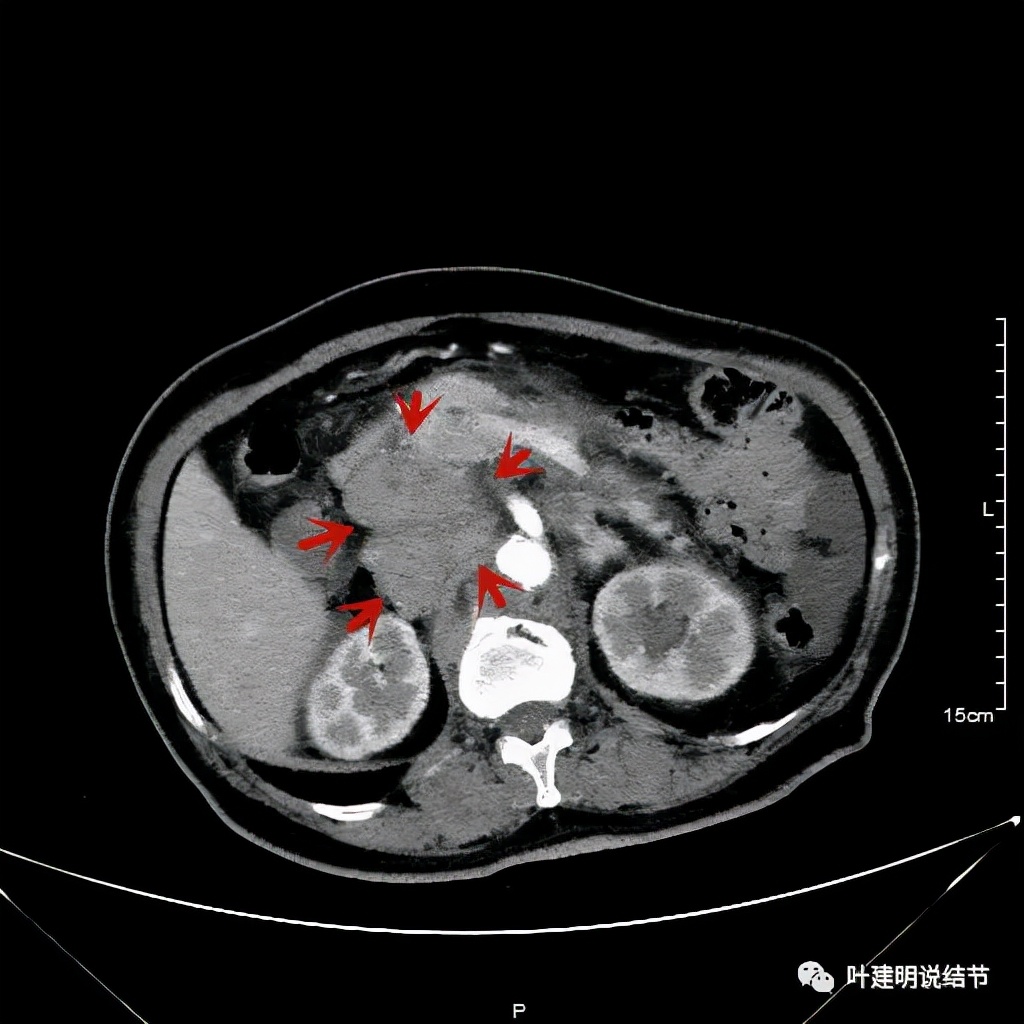

之后又再经过一个周期后的对比:

上图同样左侧是治疗前的,右侧经过2周期免疫加化疗后复查的,可见病灶缩小甚至超过9成。下面是治疗前与后来于6月底复查的: